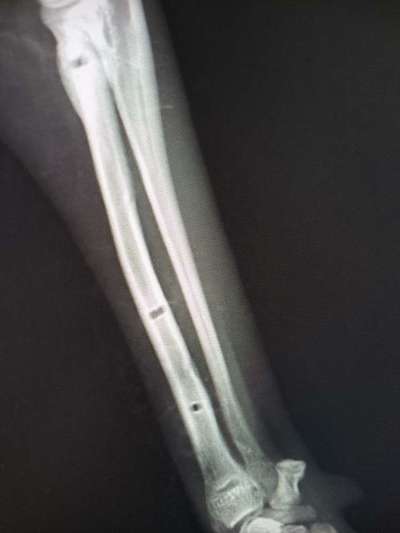

Aufgrund dieser Röntgenaufnahmen wurde am 25.10.23 beschlossen, dass der Fixateur entfernt werden kann.

Auf diesen Aufnahmen, die direkt nach der Entfernung des Fixateurs gemacht wurden, kann man gut erkennen, warum Lucy wieder / noch geschont werden muss.

Mal wieder sind es ihre dünnen Knochen in Verbindung mit ihrem Temperament, die die extreme Schonung erforderlich machen. Sonst bricht der Knochen aufgrund der Löcher, die durch die Fixateur-Drähte entstanden sind.